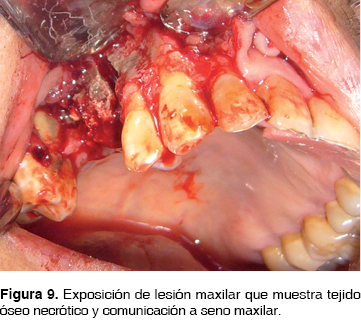

CASO 4

Masculino de 64 años de edad alérgico a la penicilina, con antecedentes de carcinoma prostático tratado mediante radioterapia prostática y cirugía 5 años antes, el cual inicia su padecimiento 2 meses previos a la consulta posterior a la extracción de segundo premolar y primer molar superior derecho, evolucionando inadecuadamente con dolor, halitosis, edema periférico facial, así como aumento de volumen en región maxilar posterior derecha. En la biometría hemática presentó hemoglobina de 11.3 g/dL, leucocitos de 4.44 cpm, glucosa de 84 g/dL. Se inicia tratamiento farmacológico con clindamicina 600 mg IV cada 8 hrs. Posteriormente se realiza hemimaxilectomía subtotal derecha bajo anestesia general inhalatoria balanceada, mediante abordaje cirunvestibular de 6 cm con disección de tejidos hasta exposición ósea, (Figura 9) observando áreas óseas de necrosis, se realiza resección ósea de 7 x 6.5 cm (Figura 10). Se verifican clínicamente bordes óseos libres de lesión y se sutura con ácido poliglicólico 3 ceros.